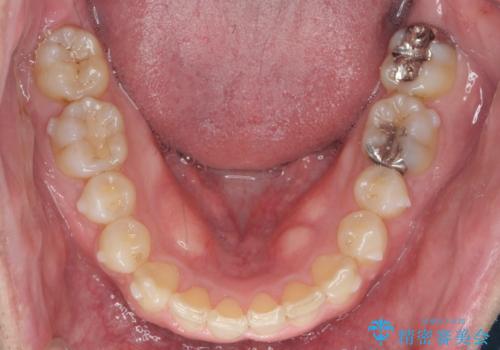

2級ディープバイト 遠心移動を伴うマウスピース矯正

・深い噛み合わせ(ディープバイト) ・2級性の咬合関係(上顎前突)・前歯のがたつき

以上のような歯並びの問題をマウスピース矯正インビザライン・カリエール・マイクロインプラント・部分ワイヤー矯正

を用いて改善していきます。

深い噛み合わせと上顎前突の状態を治すのに時間がかかりましたが、治療後は理想的で安定した咬合関係となりました。